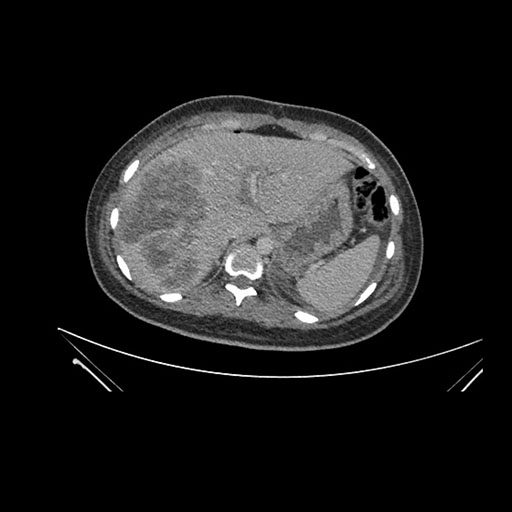

Imaging Analysis

Look through the patient's CT scan to identify any areas of concern for the necessary procedure.

Axial Venous